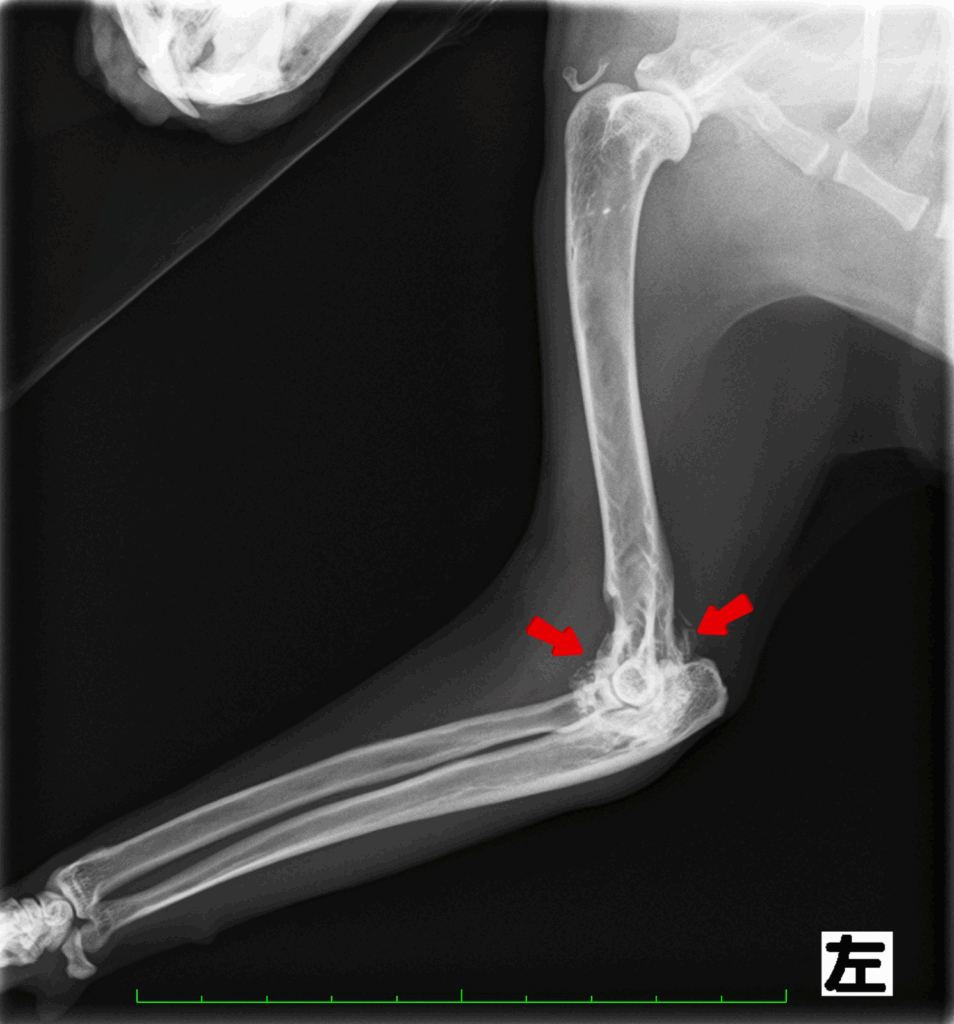

診断するにはレントゲン検査です。

関節にできた骨棘や石灰化病変を確認することで診断していきます。

特に肘関節と股関節の異常が多く認められます。